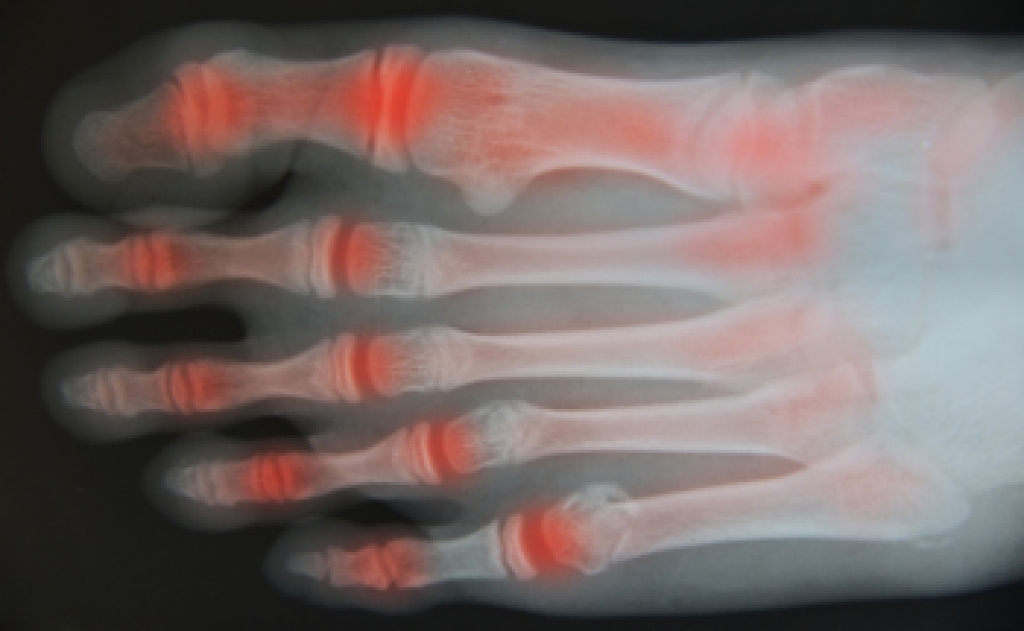

To figure out the cause of foot pain, podiatrists utilize several different methods. This can range from simple visual inspections and sensation tests to X-rays and MRI scans. Prior medical history, family medical history, and any recent physical traumatic events will all be taken into consideration for a proper diagnosis.

- Arthritis (such as Gout, Rheumatoid, and Osteoarthritis)